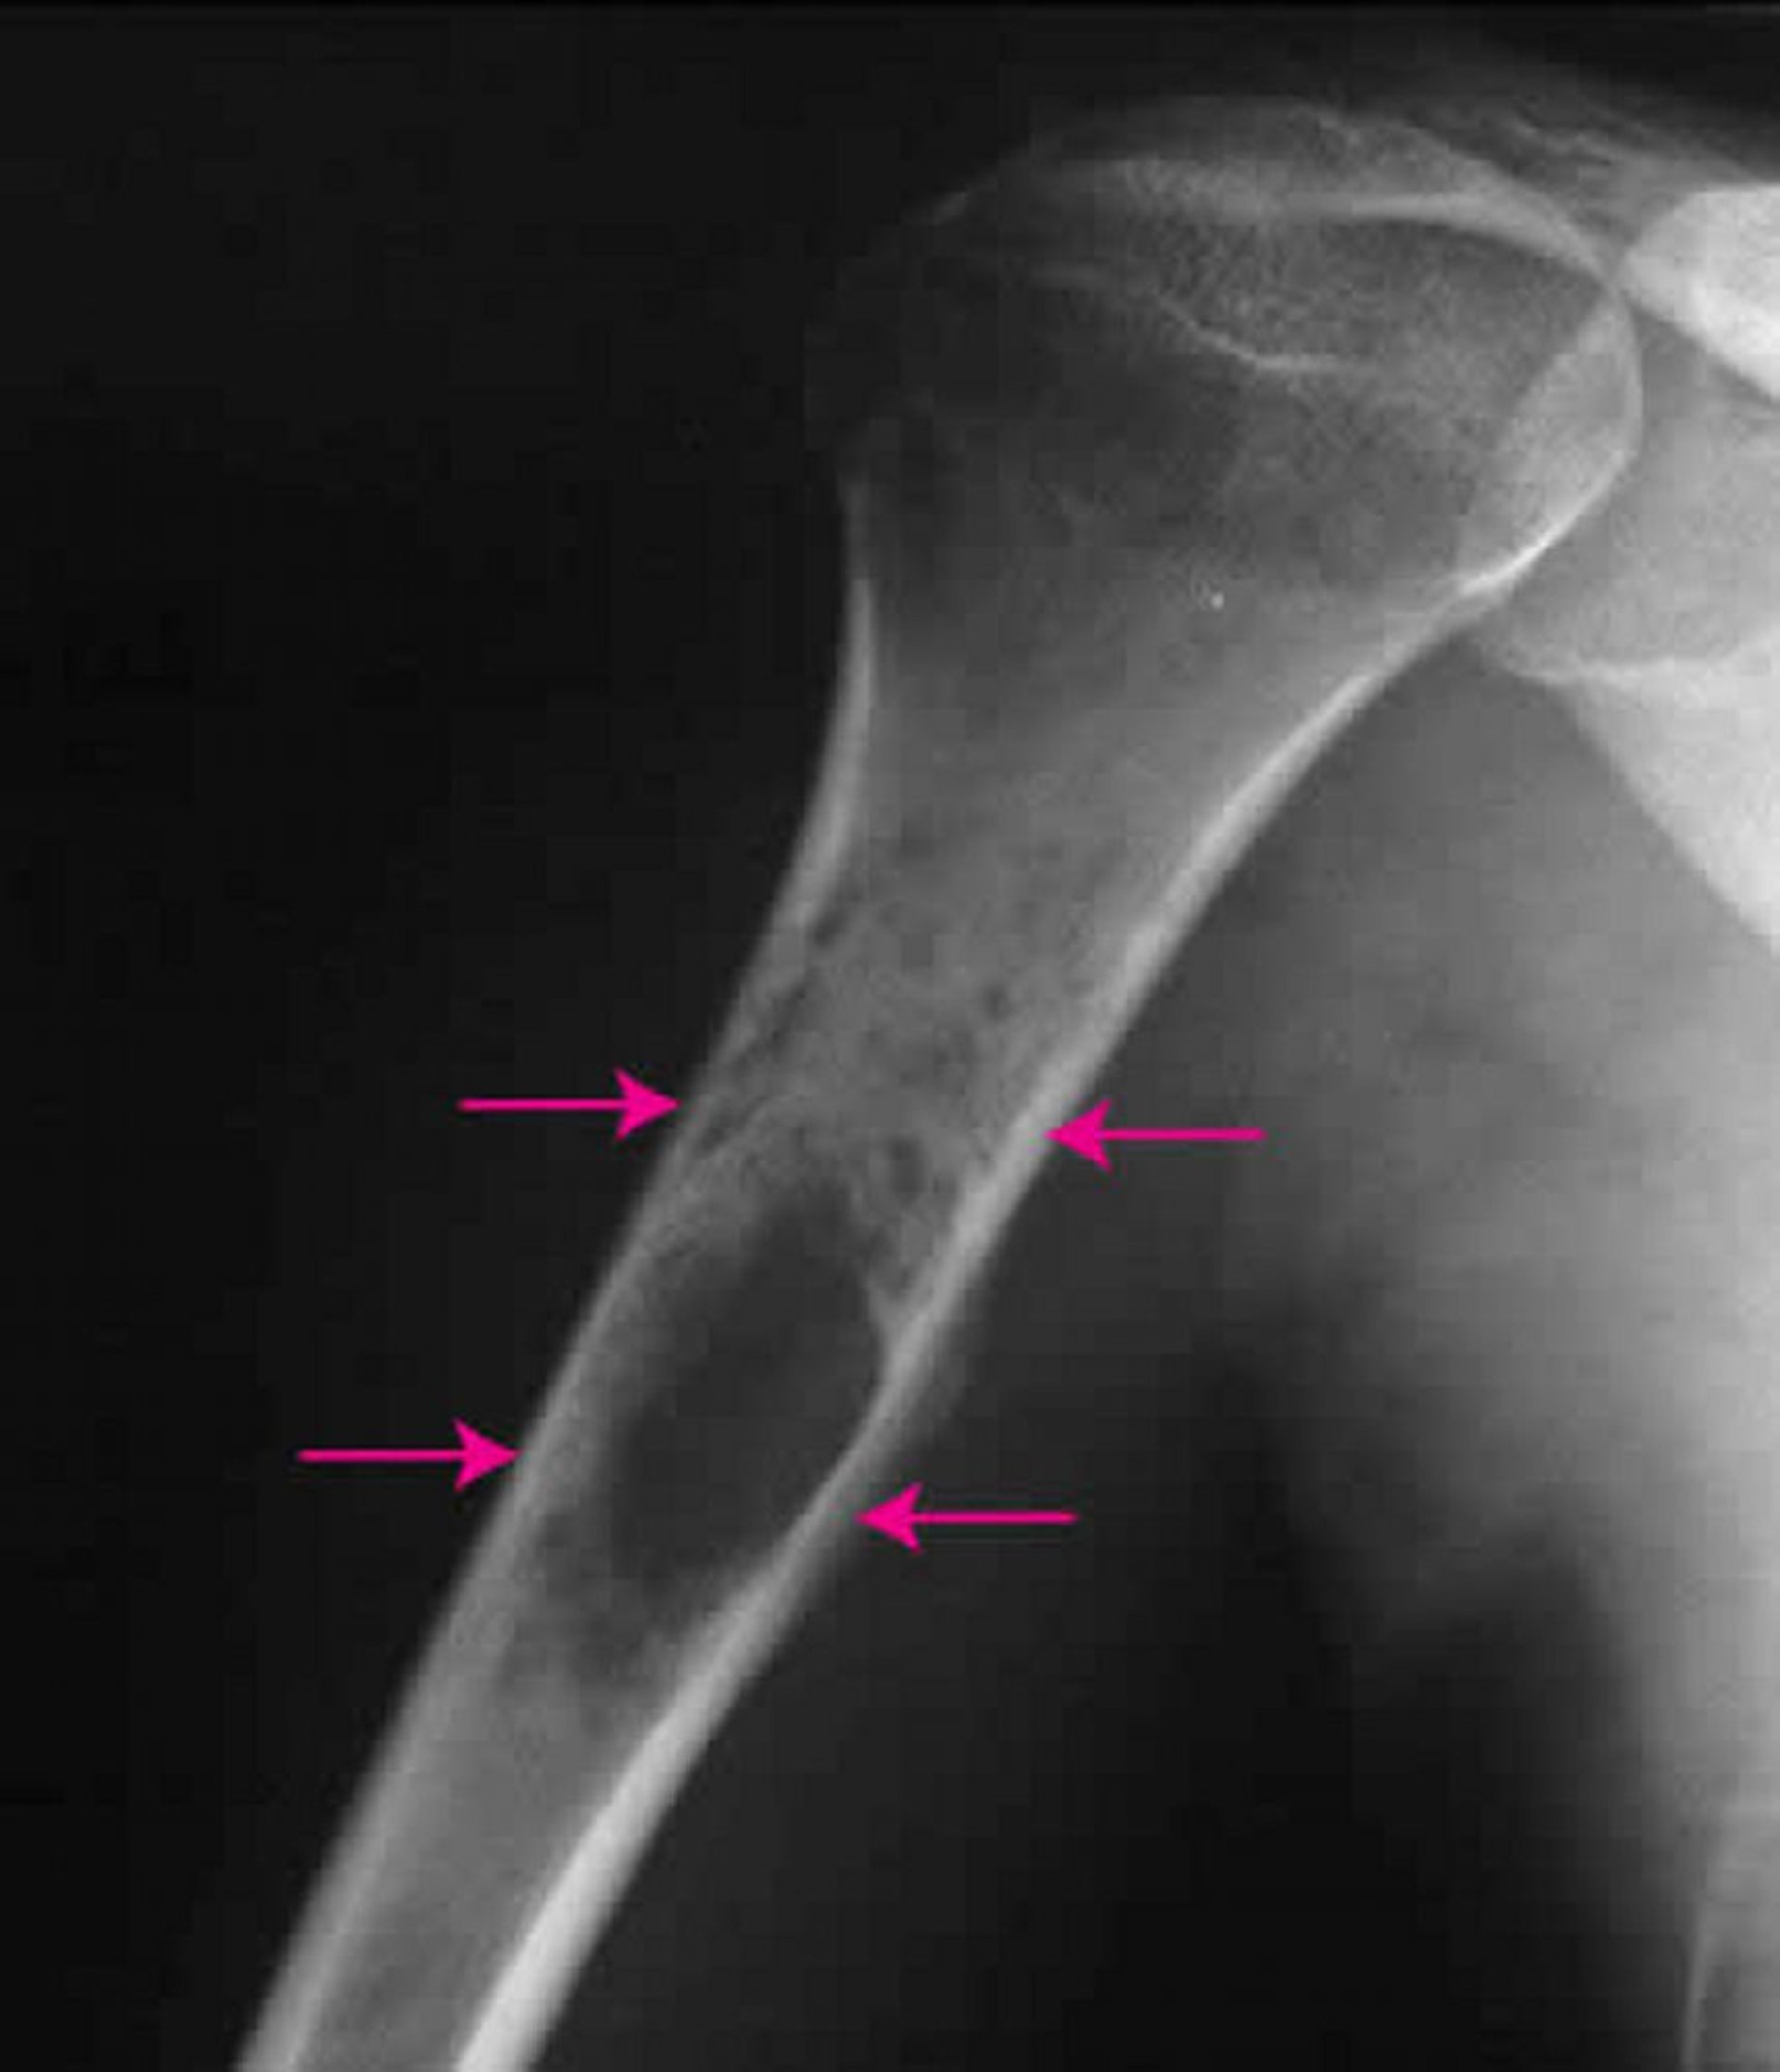

На этой рентгенограмме плеча показана саркома Юинга (стрелки) внутри плечевой кости.

Изображение любезно предоставлено д-ром Майклом Дж. Джойсом (Michael J. Joyce) и д-ром Хаканом Иласланом (Hakan Ilaslan).